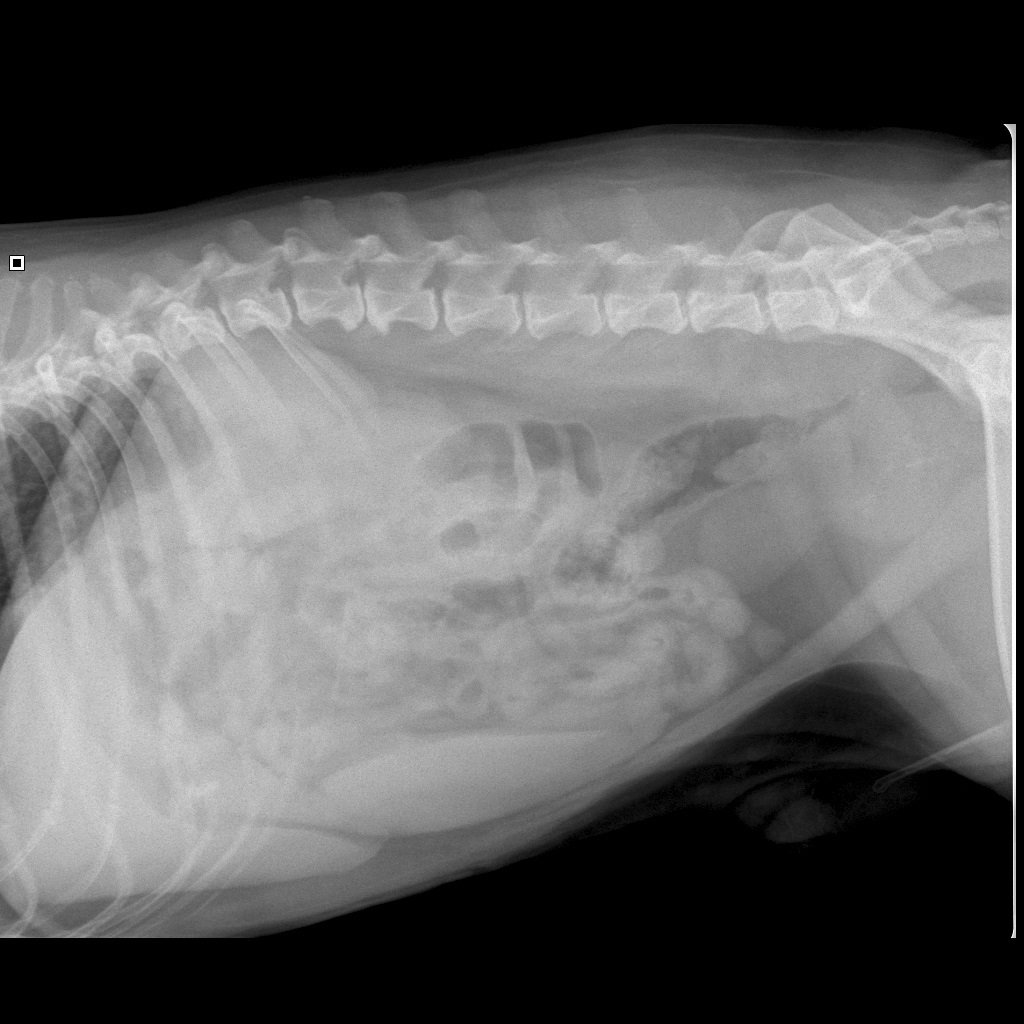

Uit het bloedonderzoek blijkt dat Jim geen problemen heeft op lever- en nierniveau. Hij heeft ook geen suikerziekte. Uit het bloed blijkt wel dat hij een stevig ontstekingsbloedbeeld heeft. We hebben vervolgens röntgenfoto's gemaakt van zijn buik. We moeten toch achterhalen waarom hij zoveel buikpijn heeft én we willen weten waar zijn prostaat is.

De röntgenfoto's zorgen uiteindelijk voor de diagnose: Jim heeft een uitgebreide prostaatontsteking. Een zeldzame aandoening die gepaard gaat met veel pijn en moeilijk poepen en plassen. Op onderstaande foto's is niet alleen de normale anatomie van het geslachtsapparaat van de reu te zien maar ook de afwijkende foto's van Jim.

De prostaat ligt als een bolletje bij de blaasuitgang en de plasbuis, die de urine vanuit de blaas naar buiten transporteert, loopt door de prostaat heen, als appel waar het klokhuis uit is. Doordat de prostaat groter en zwaarder wordt door de ontsteking is hij niet meer rectaal te voelen; de prostaat is in de buik terecht gekomen (zie onderstaande röntgenfoto's):